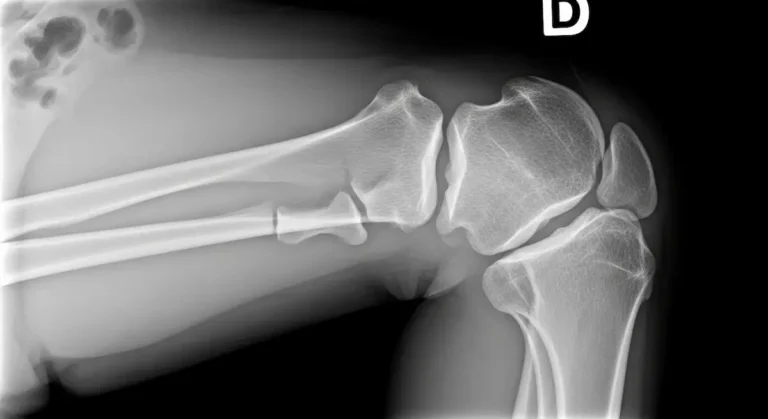

O diagnóstico é clínico, baseado na história e no exame físico. Testes que reproduzem o “beliscão” anterior com extensão ativa ajudam a identificar o foco doloroso.

A ultrassonografia pode mostrar espessamento e sinais inflamatórios da gordura, enquanto a ressonância magnética detalha o edema e descarta lesões associadas, como patela alta/baixa significativa, condropatias e tendinopatias.

Os exames complementam, mas não substituem a boa anamnese e o exame físico.